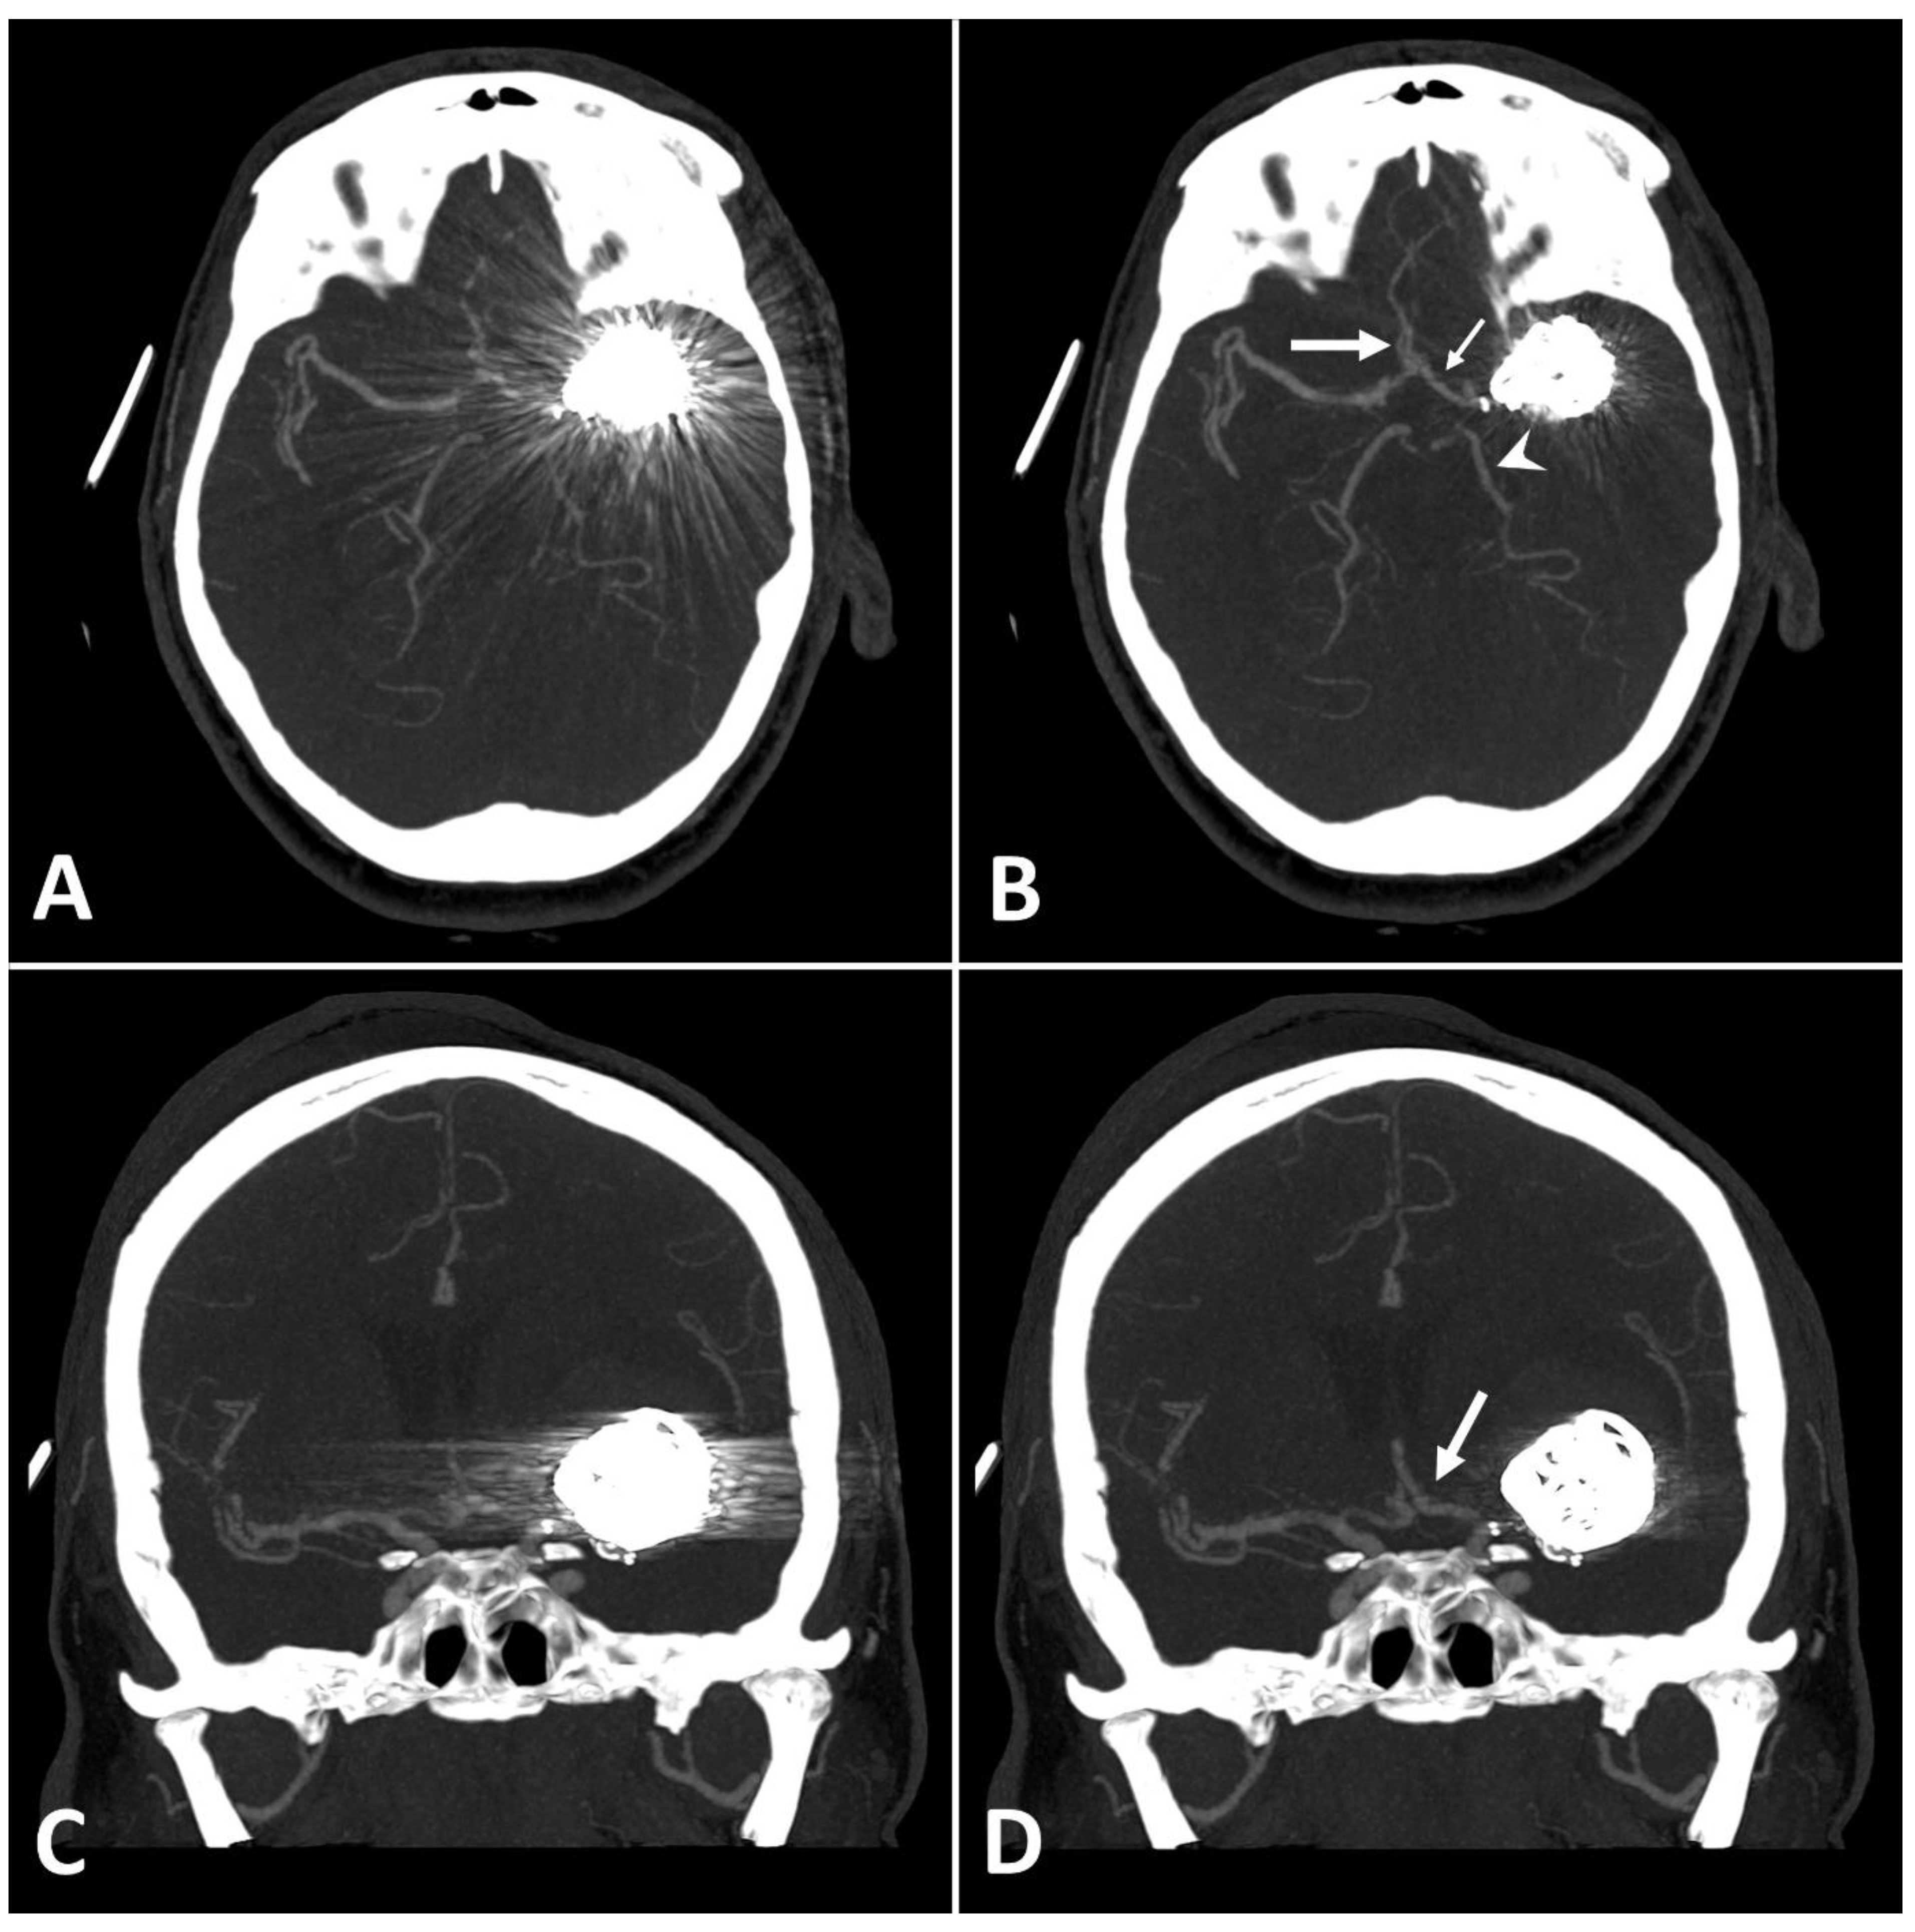

Figure 3.

Exemplary follow up UHR-CT-angiography in axial and coronal plane without (A,C) and with SEMAR (B,D) of a 48-year-old female after intracranial coil-embolization of a left sided middle cerebral artery aneurysm, demonstrate the efficacy of SEMAR in visualizing vessels adjacent to the coil package like the ipsilateral middle cerebral artery (thick arrow in (B)), the anterior cerebral artery (thin arrow in (B)), the ipsilateral posterior cerebral artery (arrowhead in (B)), and the middle cerebral artery (thick arrow in (D)). All images were reconstructed as MIP (Maximum Intensity Projection) with 12.5 mm slice thickness.

MAI in images with clips was significantly lower in close vicinity (SEMAR: 26.5 ± 55 vs. standard: 113.7 ± 95.4; p = 0.036) and more distally from the clip (SEMAR: 23.6 ± 6.5 vs. standard: 29.3 ± 16.8; p = 0.007). Figure 4 demonstrates the effects of SEMAR on images with clip-artifacts.

Figure 4.

(A,B): Exemplary follow up UHR-CT-angiography in axial plane without (A) and with SEMAR (B) of a 74-year-old female with an intracranial clip in the left middle cerebral artery. (C,D): Exemplary follow up UHR-CT-angiography in axial plane without (C) and with SEMAR (D) of a 63-year-old female with an intracranial clip in the right internal carotid artery. All images were reconstructed as MIP (Maximum Intensity Projection) with 12.5 mm slice thickness and demonstrate the effects of SEMAR on images with clip-artifacts.